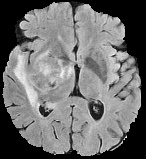

We conducted experiments on four brain imaging datasets: BraTS2017, BraTS2018, BraTS2019, and ISLES2022 [33, 34, 35, 36]. The BraTS datasets, developed for the MICCAI brain tumor segmentation challenge, contain 285, 285, and 335 labeled cases respectively, categorized into high-grade and low-grade gliomas. Each case includes 3D MRI scans from four modalities (T1, T2, FLAIR, T1c); we primarily used FLAIR. Preprocessing involved brain region cropping and intensity normalization. Dataset splits were 200/25/60 as train/val/test for BraTS2017 and BraTS2018, and 250/25/60 for BraTS2019. All experiments were conducted independently with models trained from scratch.

ISLES2022 focuses on stroke lesion segmentation in 3D multimodal MRI, with 250 cases including DWI, ADC, and FLAIR. We used DWI and split the dataset into 150 training, 40 validation, and 60 testing samples.

Quantitative Results. Tables 3–4 report results on BraTS2019, BraTS-2018, BraTS2017, and ISLES2022 datasets with limited labeled data (4% or 10%). On BraTS2019, our method outperformed most competitors in Dice, Jaccard, and 95HD, with a notable lead under the 4% setting, despite slightly lower ASD. On BraTS2018, it consistently surpassed all baselines, achieving nearly 2% higher Dice than the runner-up. It also achieved top performance on all metrics for BraTS2017, highlighting strong robustness and generalization. For ISLES2022 with 10% labeled data, our method significantly outperformed DAE-MT and closely matched the fully supervised model.

Qualitative Results. Figures 4, 3 present visual comparisons of the predicted segmentation results from our method and other baselines on the middle slice of the BraTS2018, BraTS2019, and ISLES2022 datasets. Our method demonstrates greater robustness and better coverage of the ground truth regions, particularly in areas where other methods fail to identify lesions and incorrectly classify them as background. Furthermore, our approach yields more accurate boundaries and preserves the overall shape of the target structures more effectively than competing methods.